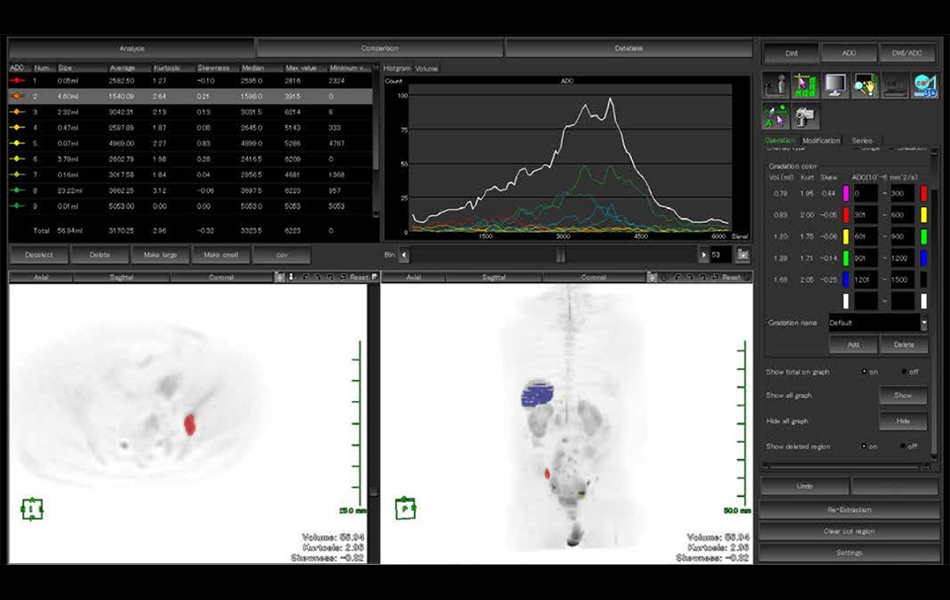

DWI Body Score and DWI Stitching (7.15.8)

The Body DWI Score application is a post processing application of MR images that is intended to assist physicians in their review. This application supports visualization of threshold regions on Whole Body DWI (Diffusion-Weighted Imaging) images and ADC maps while providing measurement tools for the threshold regions. The DWI Stitching application is a pre-processing application for Body DWI Score that is intended to stitch multiple MR images and regions using different slice positions for each scan.